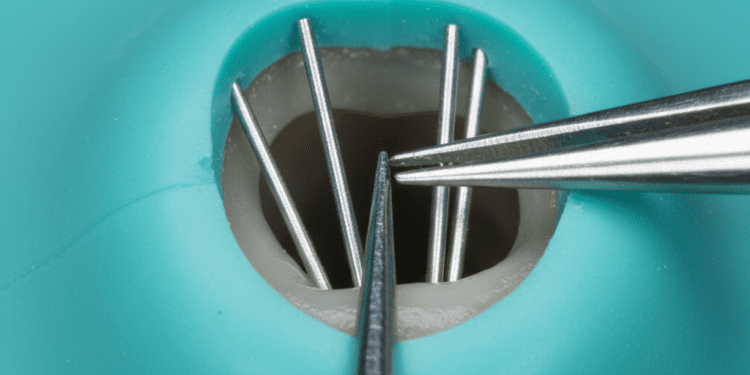

O diagnóstico é realizado por meio da anamnese, exame clínico e testes sensoriais. O dentista deverá analisar os sintomas descritos pelo paciente e avaliar a vitalidade da polpa com métodos que incluem:

- Teste de sensibilidade térmica: Aplicação de frio para verificar a resposta da polpa;

- Teste elétrico de vitalidade: Utilizado para medir a resposta elétrica da polpa;

- Exame radiográfico: Para verificar a presença de cáries, lesões e alterações periapicais;

- Inspeção clínica: Análise de restaurações, presença de fissuras, fraturas ou desgaste dentário.

Os sinais indicativos de pulpite reversível são sensibilidade rápida e passageira ao estímulo, ausência de dor espontânea e exames complementares que confirmem a integridade pulpar.